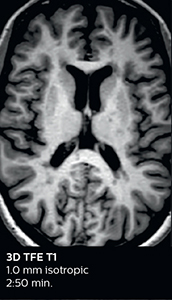

A two year follow-up scan of a CPA meningioma using both Ingenia 3.0T without CS and Ingenia Elition 3.0T with Compressed SENSE allows for a nice comparison to demonstrate the protocol improvements achieved on the Elition: 3D FLAIR has a shortened scan time, improved SNR and still the same spatial resolution. BrainView (3D T1 TSE) has improved spatial resolution and SNR with shortened scan time. For 3D T2 Drive the spatial resolution has been improved. 3D THRIVE used to have an interpolated 0.8 mm slice thickness, but true thickness at 1.6 mm, so that axial slices displayed a decent quality, but reformats were suboptimal. Compressed SENSE is used on Elition to improve spatial resolution and reduce the non-interpolated slice thickness to allow smoothly reformatted images. Total scan time (adding SmartBrain and an additional b2000 diffusion) was 13:19 on Ingenia, and is now reduced to 10:42 on Ingenia Elition.

Ingenia 3.0T (without Compressed SENSE)

3D FLAIR 1.0 x 1.0 x 1.0 mm* 4:24 min.

3D TSE T1w 1.0 x 1.0 x 1.2 mm* 2:40 min.

3D T2w Drive 0.8 x 0.8 x 1.0 mm* 3:05 min.

3D T1w THRIVE 0.8 x 0.8 x 1.6 mm* 1:30 min.

Ingenia Elition 3.0T with Compressed SENSE

3D FLAIR 1.0 x 1.0 x 1.0 mm* 2:50 min.

3D TSE T1w 1.0 x 1.0 x 1.0 mm* 2:10 min.

3D T2w Drive 0.7 x 0.7 x 0.7 mm* 2:52 min.

3D T1w THRIVE 0.7 x 0.7 x 0.8 mm* 1:30 min.

*true voxel size, without interpolation